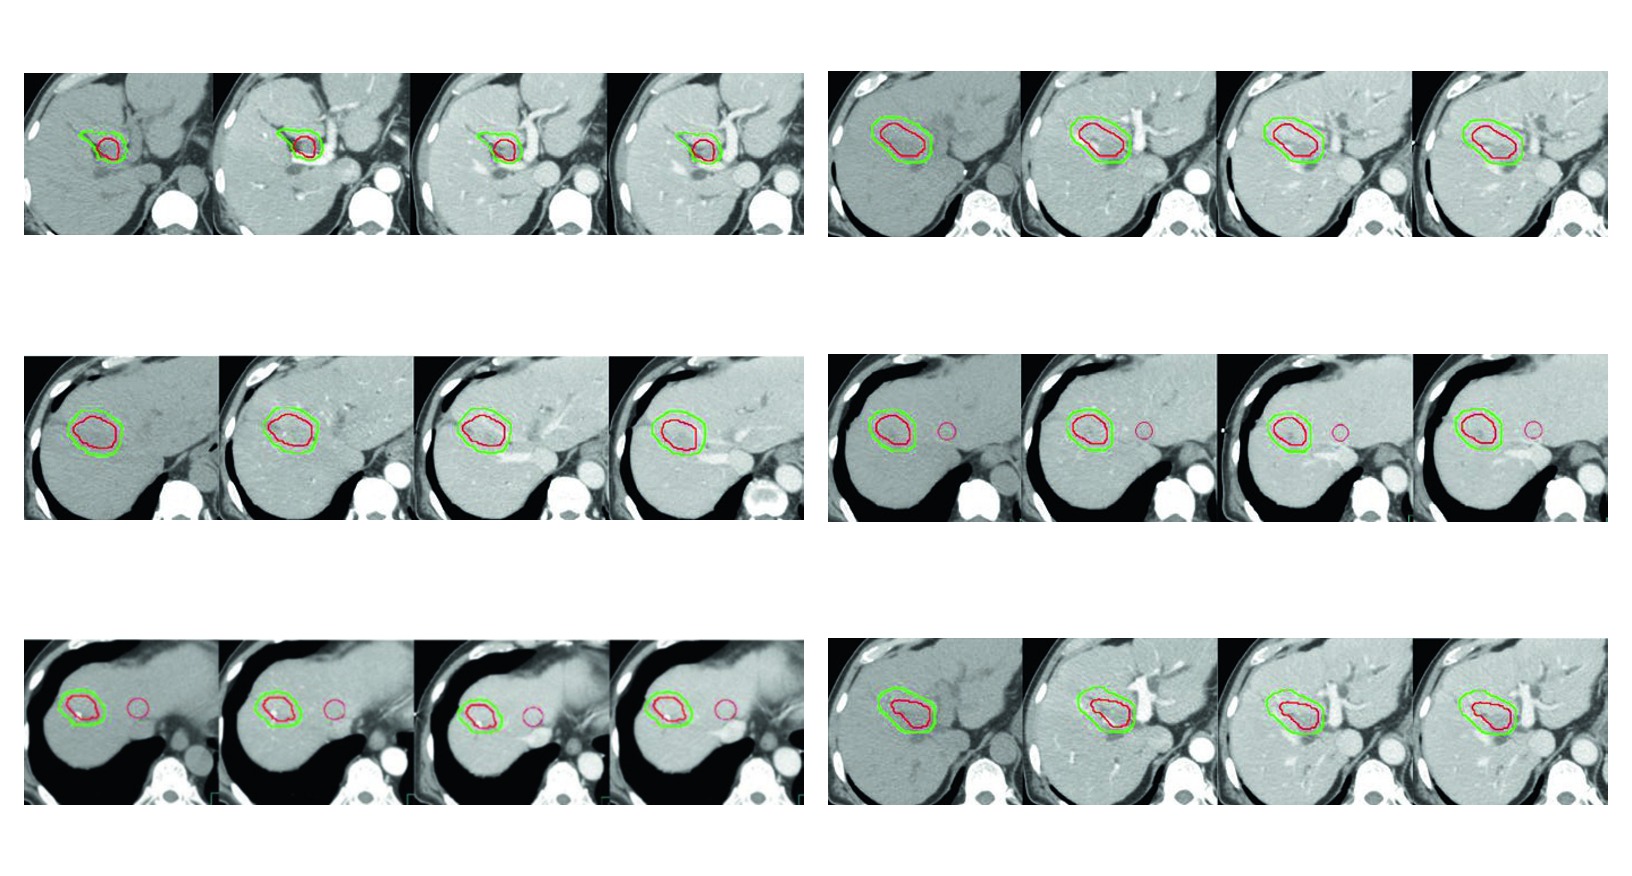

A Figura 17.3 traduz bem essa filosofia. O caso de recorrencia apos cirurgia e radiofrequencia, com alto risco de lesao de ducto biliar pela ablacao, usa simulacao com fases sem contraste, arterial, portal e venosa tardia, sempre em apneia. O CTV em verde inclui o tumor contrastado mostrado como GTV em vermelho, uma margem de 5 mm no parenquima hepatico e uma margem intravascular de 3 mm ao redor do GTV. Nao ha expansao gratuita. Ha resposta a um contexto clinico especifico.

As quatro figuras do capitulo funcionam como exemplos aplicados da mesma logica. Todas usam simulacao multiphasica com coordenacao de apneia para imobilizacao do figado. Todas mostram GTV em vermelho e CTV em verde. E todas deixam claro que a margem muda quando entram em cena trombo tumoral, zona previamente ablada, area embolizada ou risco de extensao ao longo do vaso.

Figura 17.3

No terceiro, o risco biliar apos cirurgia e radiofrequencia reforca que delineamento e planejamento nao podem ser separados. O contorno ja nasce condicionado por uma historia local que influencia seguranca, distribuicao de dose e escolha de margem.